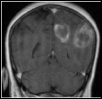

Disparition de lésions cérébelleuses chez un migraineux ?

Migraineuse de 45 ans ayant des antécédents d’HTA contrôlée, de période de migraine chronique avec abus médicamenteux puis retour à une migraine épisodique après prescription de topiramate, qui se plaint récemment d’une aggravation de ses céphalées, d’une vision trouble, d’épisode de sensation vertigineuse. Le fond d’œil est normal. L’IRM montre deux hypersignaux dans l’hémisphère cérébelleux droit en T2, en FLAIR, en diffusion suggérant deux probables infarctus cérébelleux.